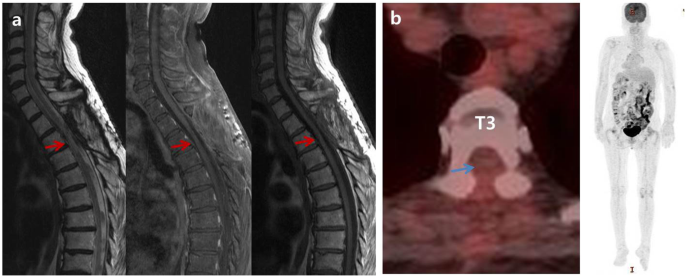

Under the laminectomy of T2-T4 and opening the dura, enlarged thoracic cord with a normal superficial appearance was noted. Midline myelotomy allowed the identification of a white-gray-colored and soft-natured mass lesion with an ill-defined boundary (Fig. 2). The mass lesion was located at the central portion with a slight deviation on the right inside the cord. Gross total removal was achieved under intraoperative neuro-monitoring with no signal change. The patient showed no change in neurologic function after surgery. Histological examination revealed diffuse infiltration of foamy (lipid-laden) histiocytes with uniform nuclei and abundant cytoplasm (Fig. 3a). On immunohistochemical staining, foamy histiocytes showed diffuse and strong expression of CD163 and CD68 (histiocytic marker) (Fig. 3b), and there were negative for CD1a, S100, and BRAFV600E mutation (Fig. 3c). No systemic lesions were noted on the preoperative radiological examinations; therefore, we confirmed this case as variant ECD with isolated intramedullary involvement. There was no recurrence or new development of mass lesions on MRI and whole-body FDG-PET/CT at 12-month follow-up (Fig. 4). The patient became self-standing and aid-walkable with recovery of anal tone and sensory impairments. Unfortunately, sudden paraplegia occurred again at 18-month follow-up, which was confirmed that it was developed by unknown originated thoracic cord infarction. There was no evidence related with recurrence or new lesion of ECD on spine MRI and whole-body FDG-PET/CT (Fig. 5).

On the initial radiological findings after development of paraplegia at 18-month follow-up (a), magnetic resonance imaging (MRI) showed swelling, extensive edema (red arrows), and contrast enhancement (blue arrows) of whole thoracic cord including previous tumor surgical lesion on T2-4. However, there is no evidence of recurrence or new lesion on whole-body 18F-fluorodeoxyglucose positron emission tomography/computed tomography. On the 2-week follow-up MRI, there was significant reduction of edema and contrast enhancement in thoracic cord (red and blue arrows) (b), which was almost disappeared on the 5-week follow-up MRI (c)